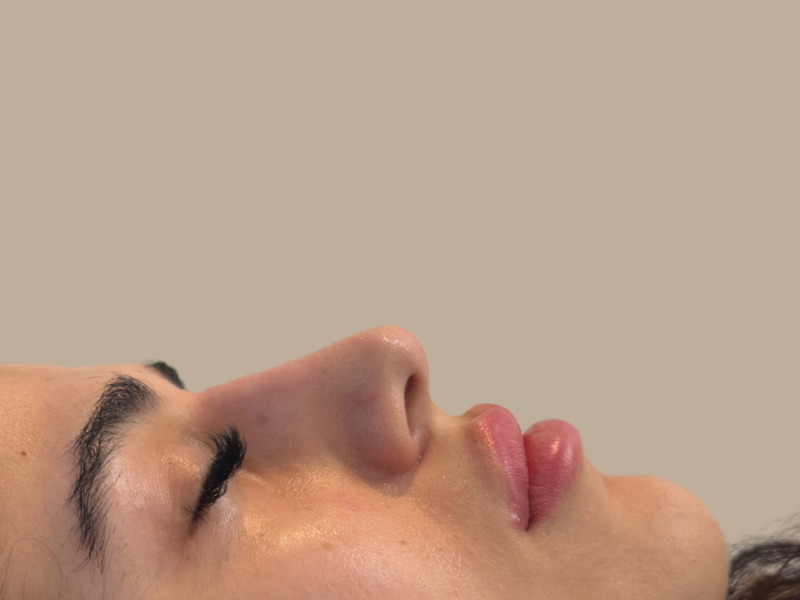

לפני ואחרי

לפניכם דוגמה למטופלות רשת מרפאות פרופורציה:

עבור מטופלים אשר עברו ניתוח אף ומרגישים כי התוצאה עדיין אינה מיטבית, הליך פיסול האף מאפשר ביצוע של מקצה שיפורים נקודתי למילוי וטיפול באסימטריה. ניתן לגשת לייעוץ אצל רופא אסתטיקה בעל ניסיון בתחום בנוגע לפיסול אף בתום שנה מהניתוח, לאחר החלמה מלאה וההתייצבות תצורת האף.